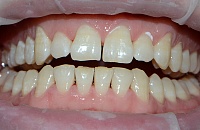

Работы врача